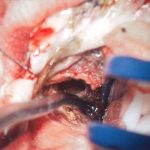

手術写真

手術前

手術中

手術後